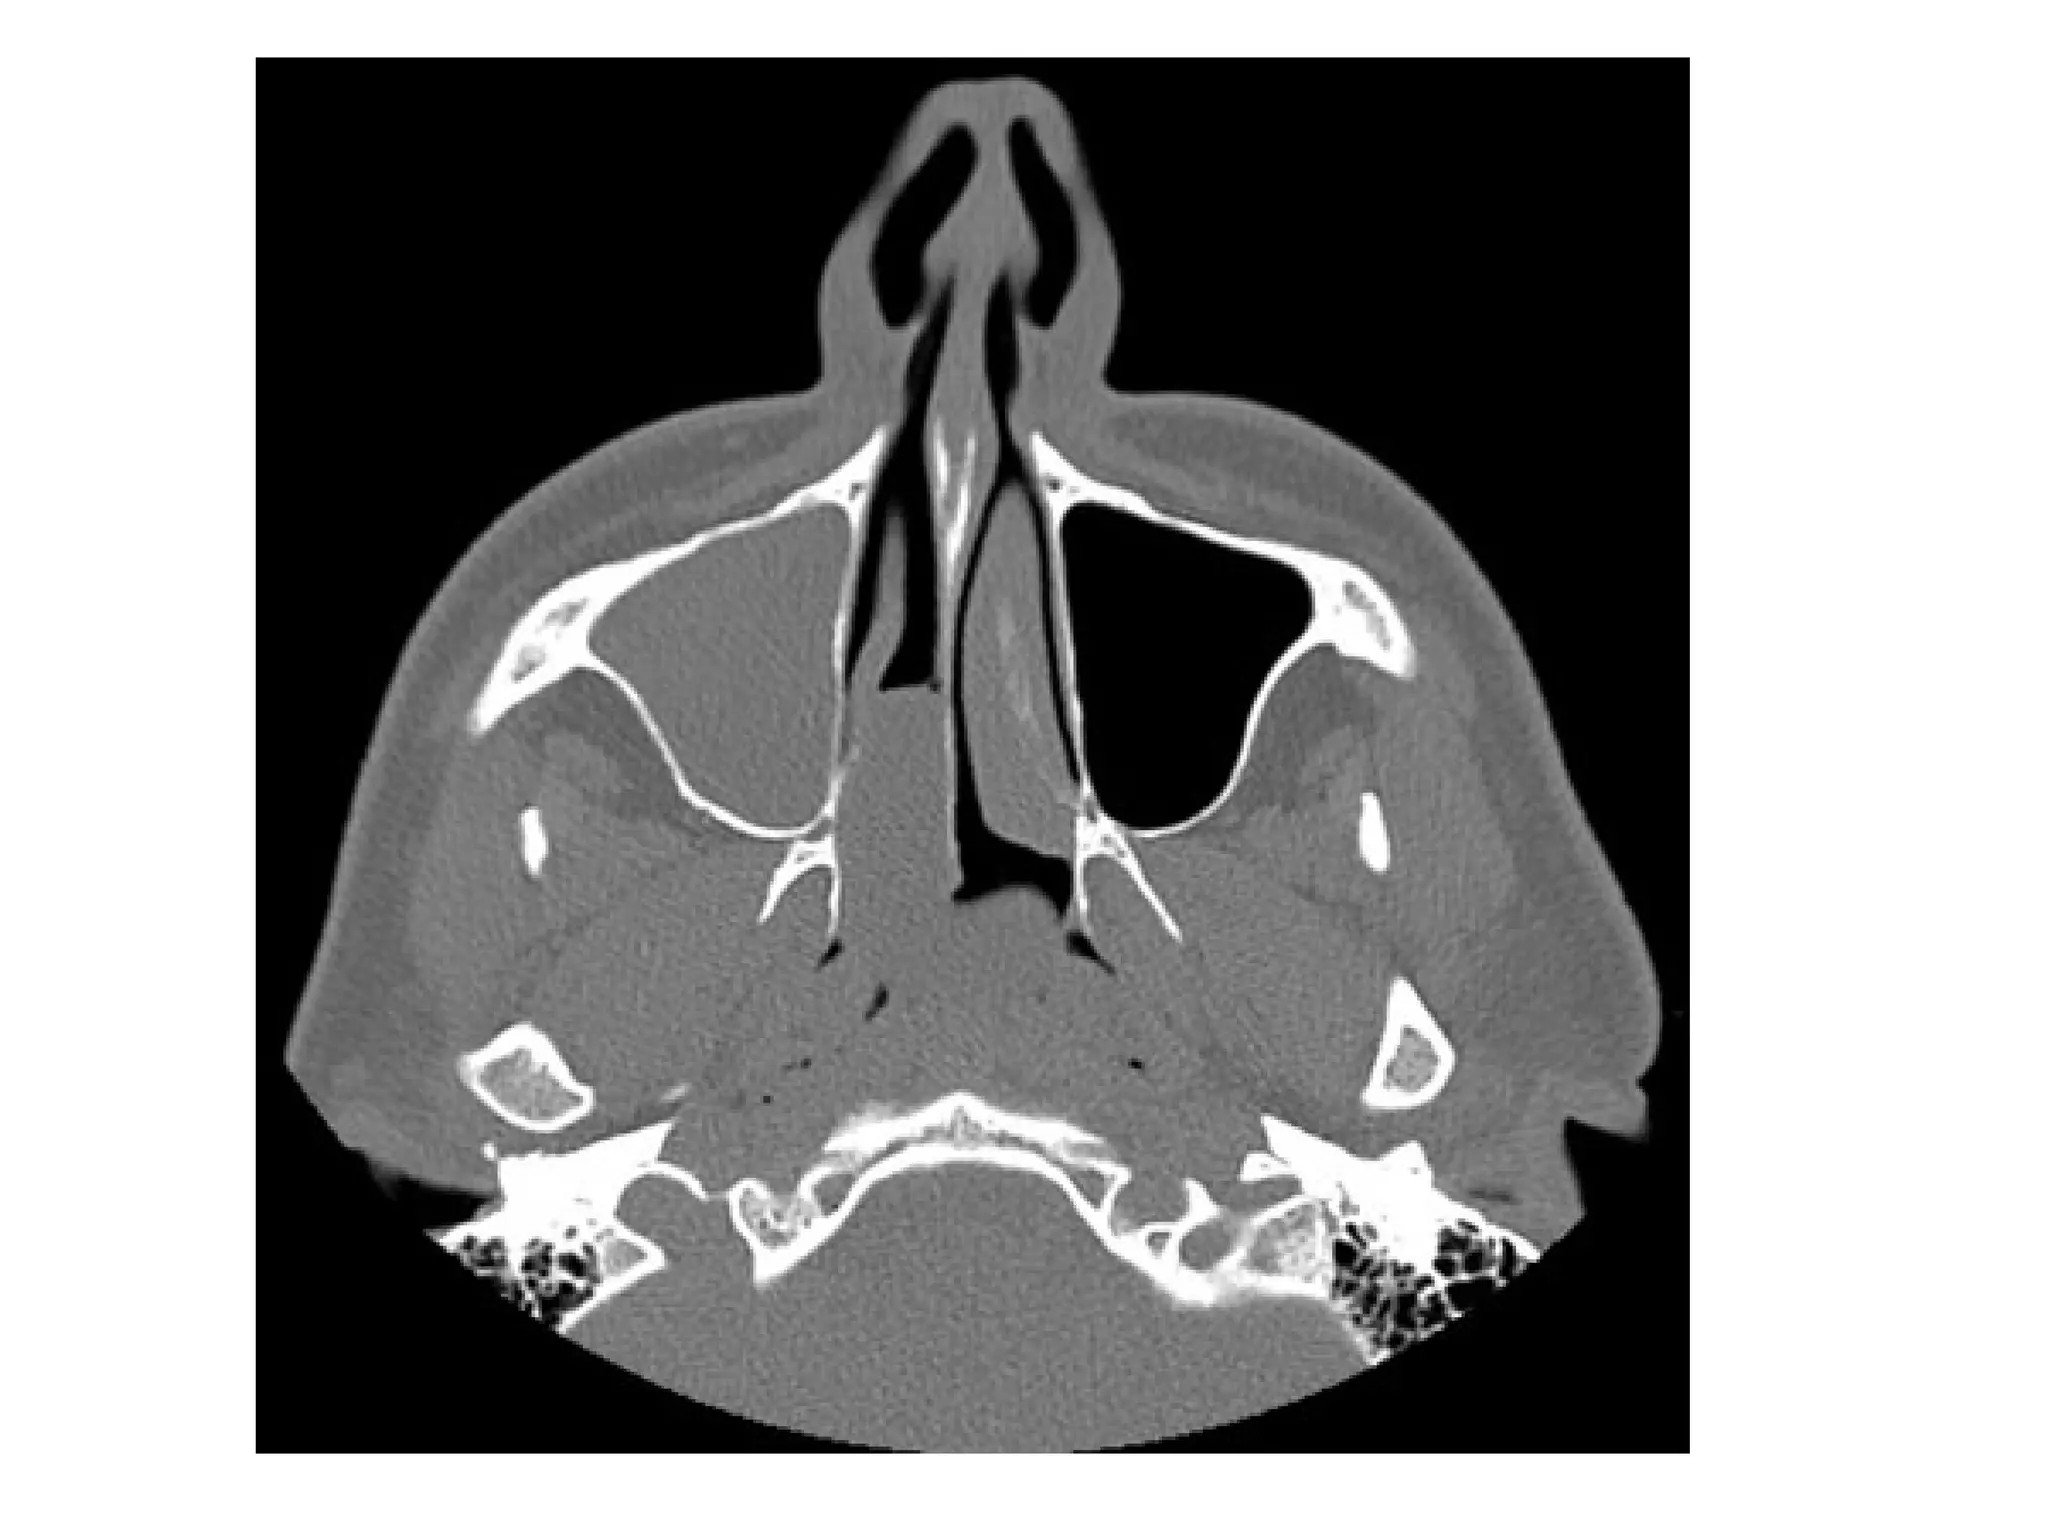

Antrochoanal polyp, axial (A) and coronal (B) CT show complete

opacification of the right maxillary sinus with extension into the right

middle meatus and inferior aspect of the right nasal cavity, there is

thickening of the sinus walls but no sinus expansion